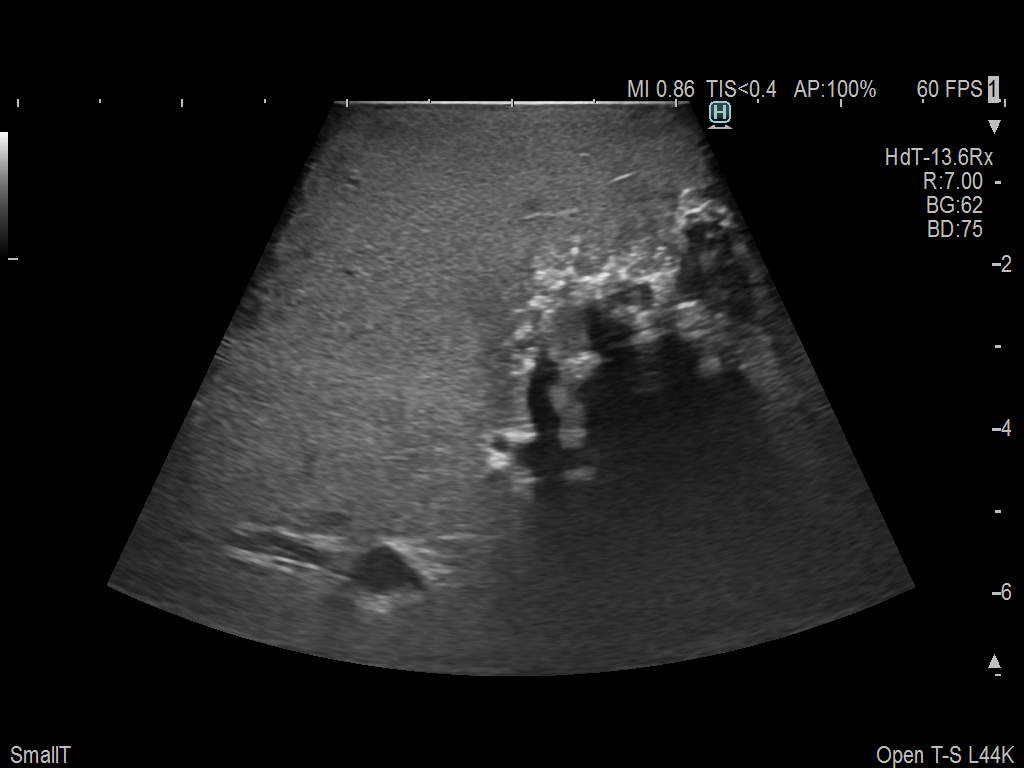

Liver Ablation Procedure using L44K

Linear array side-fire “T” transducer for open surgical procedures, providing exceptional near and far-field resolution.